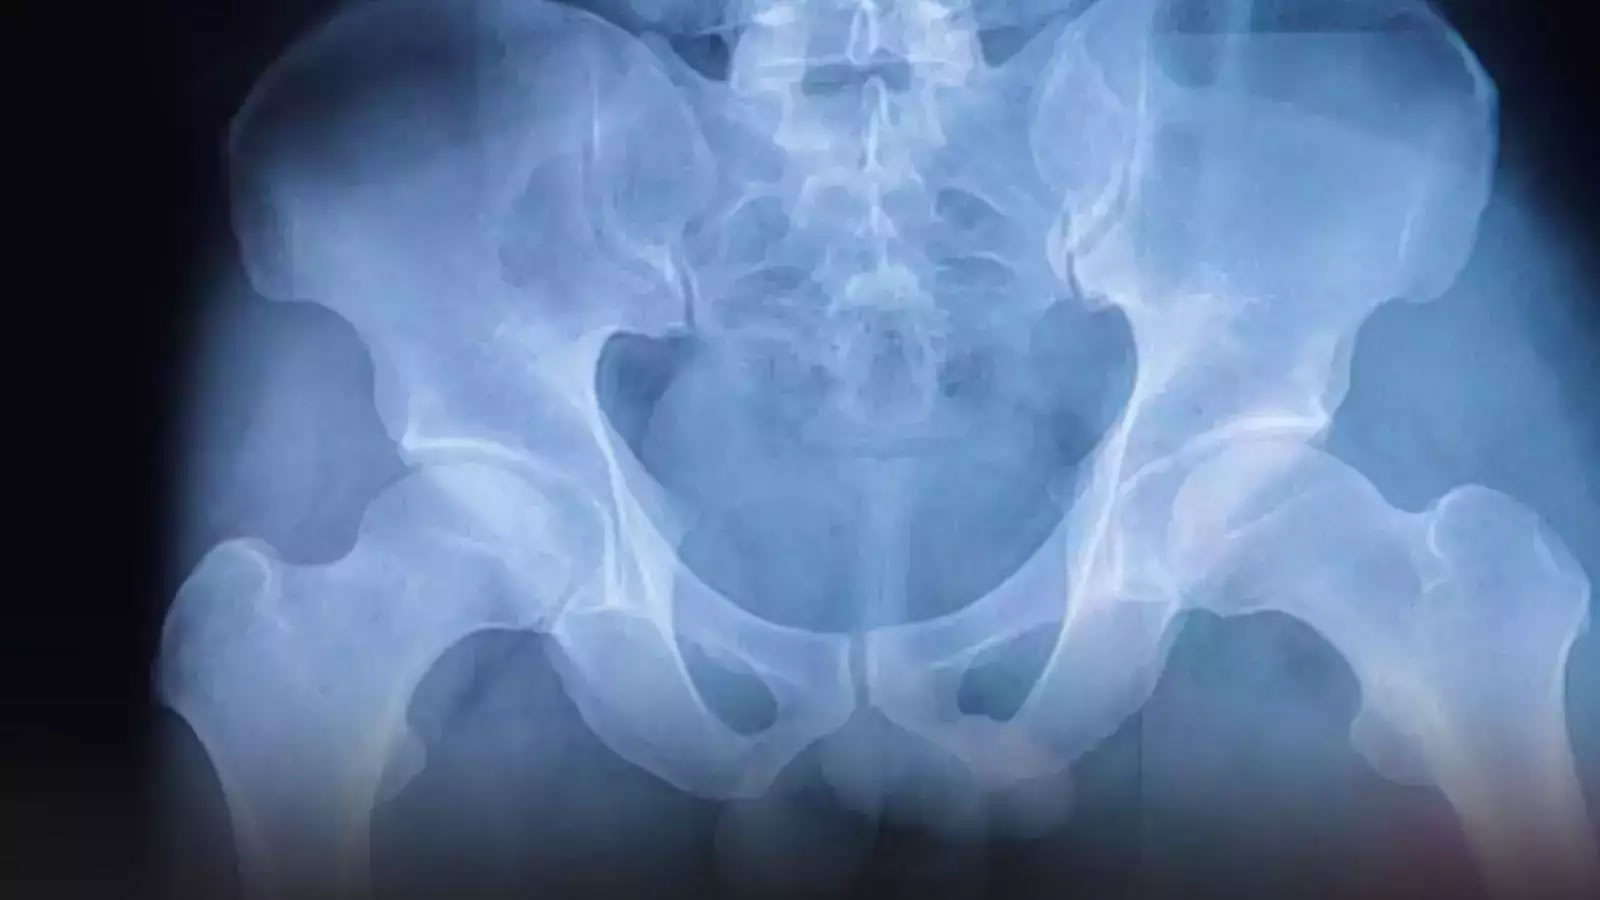

(蜘蛛网eeook.com)据cnBeta:根据利兹大学食品科学家进行的一项新研究,增加蛋白质摄入量和定期饮用茶或咖啡可能有助于降低女性髋部骨折的风险。研究发现,每天增加25克蛋白质与髋部骨折的风险平均减少14%有关。此外,该研究显示,每增加一杯茶或咖啡的摄入,都与遭受髋部骨折的风险减少4%有关。

研究人员在《临床营养学》杂志上撰文指出,对于体重不足的妇女来说,保护性的好处更大,每天增加25克的蛋白质可以使她们的风险降低45%。

研究组中仅有3%以上的妇女经历了髋部骨折。该调查--食物、营养素和髋部骨折风险。对中年妇女的前瞻性研究--是基于对超过26000名妇女的大型观察分析。

在参与研究的26318名妇女中,有822例髋部骨折,即3.1%。